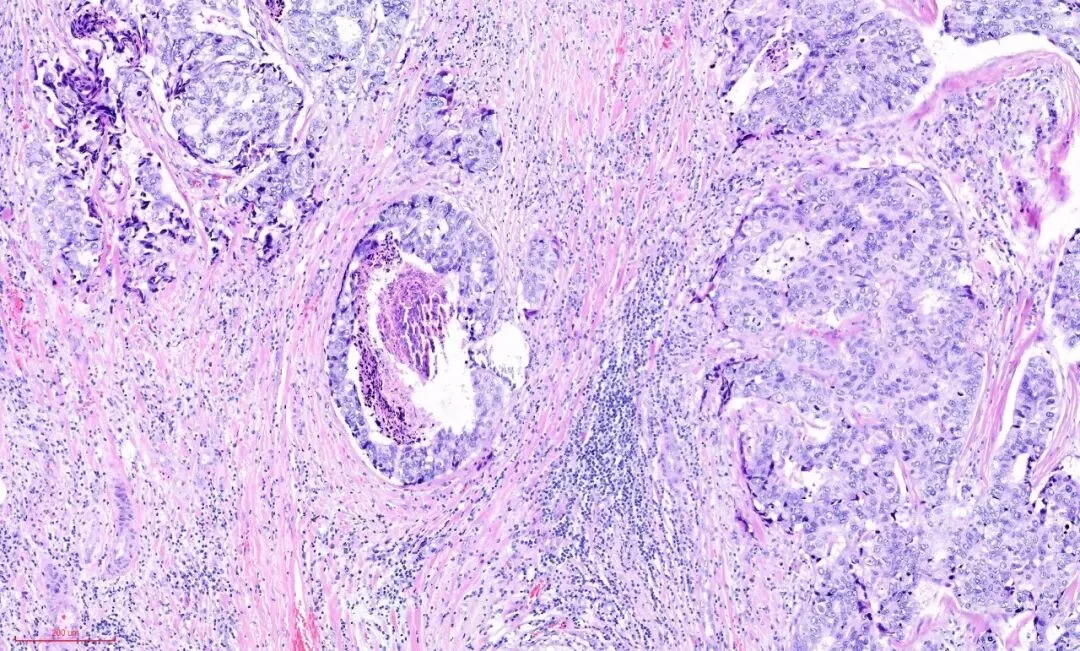

这是另一例,低倍镜下观察, 硬化型腺病的部分似乎保持小叶中心性的分布模式,病变周围是正常的小叶,如图:

在视野中心看到粉染的硬化的纤维结缔组织,其内有受挤压变形的腺体,其周边有增生的腺体,如下图:

转高倍,看到腺上皮肌上皮的双层结构,如下图: